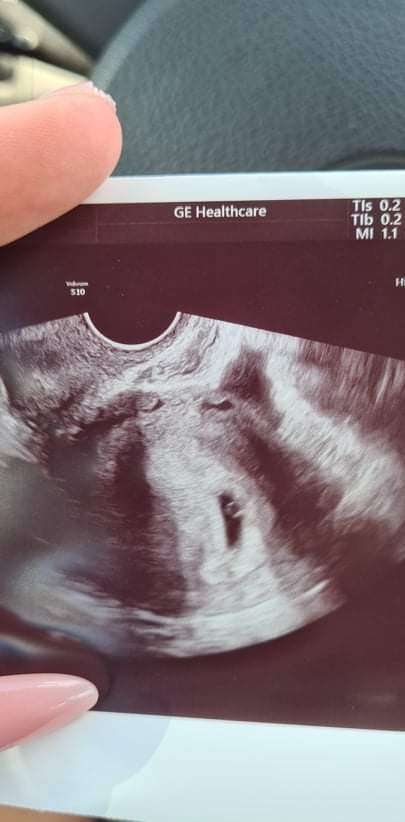

Czesc jestem w 6tc i po ostatniej wizycie pani doktor która najpierw mnie skomentowała ze w krótkich spodenkach się nie przychodzi do lekarza bo ona czuje się obrazona pierwszy raz się z czym takim spotkalam zdenerwowana przebadała mnie i mówi ze tu coś jest nie tak bo nie ma serca ani głowy ze chyba bezczaszkowiec I ona się pod tym nie podpisze i dala mi skierowanie do szpitala na szczegółowe badanie USG ( na skierowaniu napisala niewyraźny obraz usg chyba ciąża obumarla)Poszlam ale p.doktor powiedzial ze dopiero za tydzień możemy zobaczyć czy wszystko ok bo to wczesna ciąża.Chce jeszcze dodać ze tydzień temu bylam prywatnie i lekarz na usg powiedział ze widzi sam pęcherzyk.Co Wy o tym myślicie i uważacie bo jestem bardzo zdenerwowana szczegółowe badanie bede miec 4sierpnia.Jestem załamana.Ilona 40lat druga ciąża.

Poczekaj na kolejne badania. Jak lekarz może w 6 TC ocenić czy bezczaszkowiec czy nie, skoro tak naprawdę na zdjęciu USG zarodek jest maleńka kropeczka, nie widać jeszcze kończyn itp. za szybko na takie wyroki.